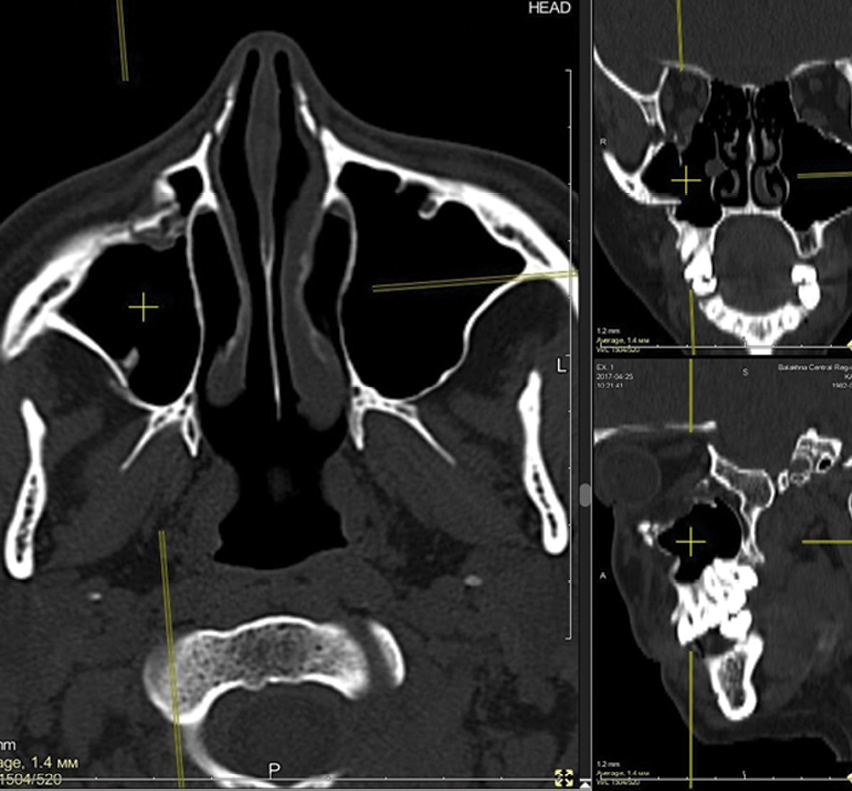

Стандартная толщина среза при КТ ГМ составляет 5 мм, шаг в зависимости от аппарата – 0,1–1 мм [10, 20]. При подозрении на переломы костей лицевого скелета (рисунки 1 и 2) проводят дополнительное сканирование толщиной среза 1–2 мм с последующей MPR и 3D- реконструкцией [1, 12, 15, 21].

Рисунок 1. КТ костей лицевого скелета в MPR. Перелом верхнечелюстной пазухи справа.

Рисунок 2. КТ костей лицевого скелета в MPR. Перелом верхнечелюстной пазухи с обеих сторон и двусторонний гемосинус.